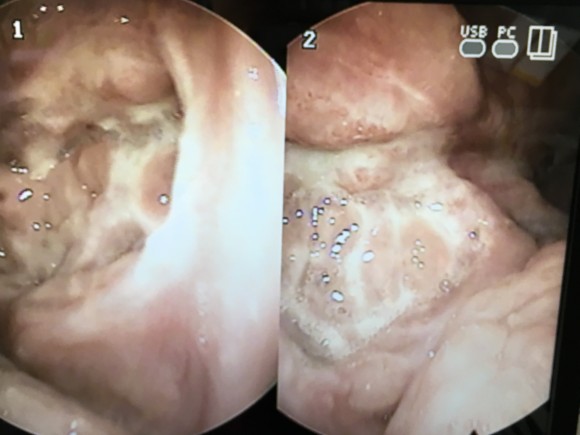

상단:편도와의 윗부분에 결석이 끼여있는 모습과 제거한 편도 결석, 하단:고주파 시술과 PITA 시술 일주일과 3주차의 모습